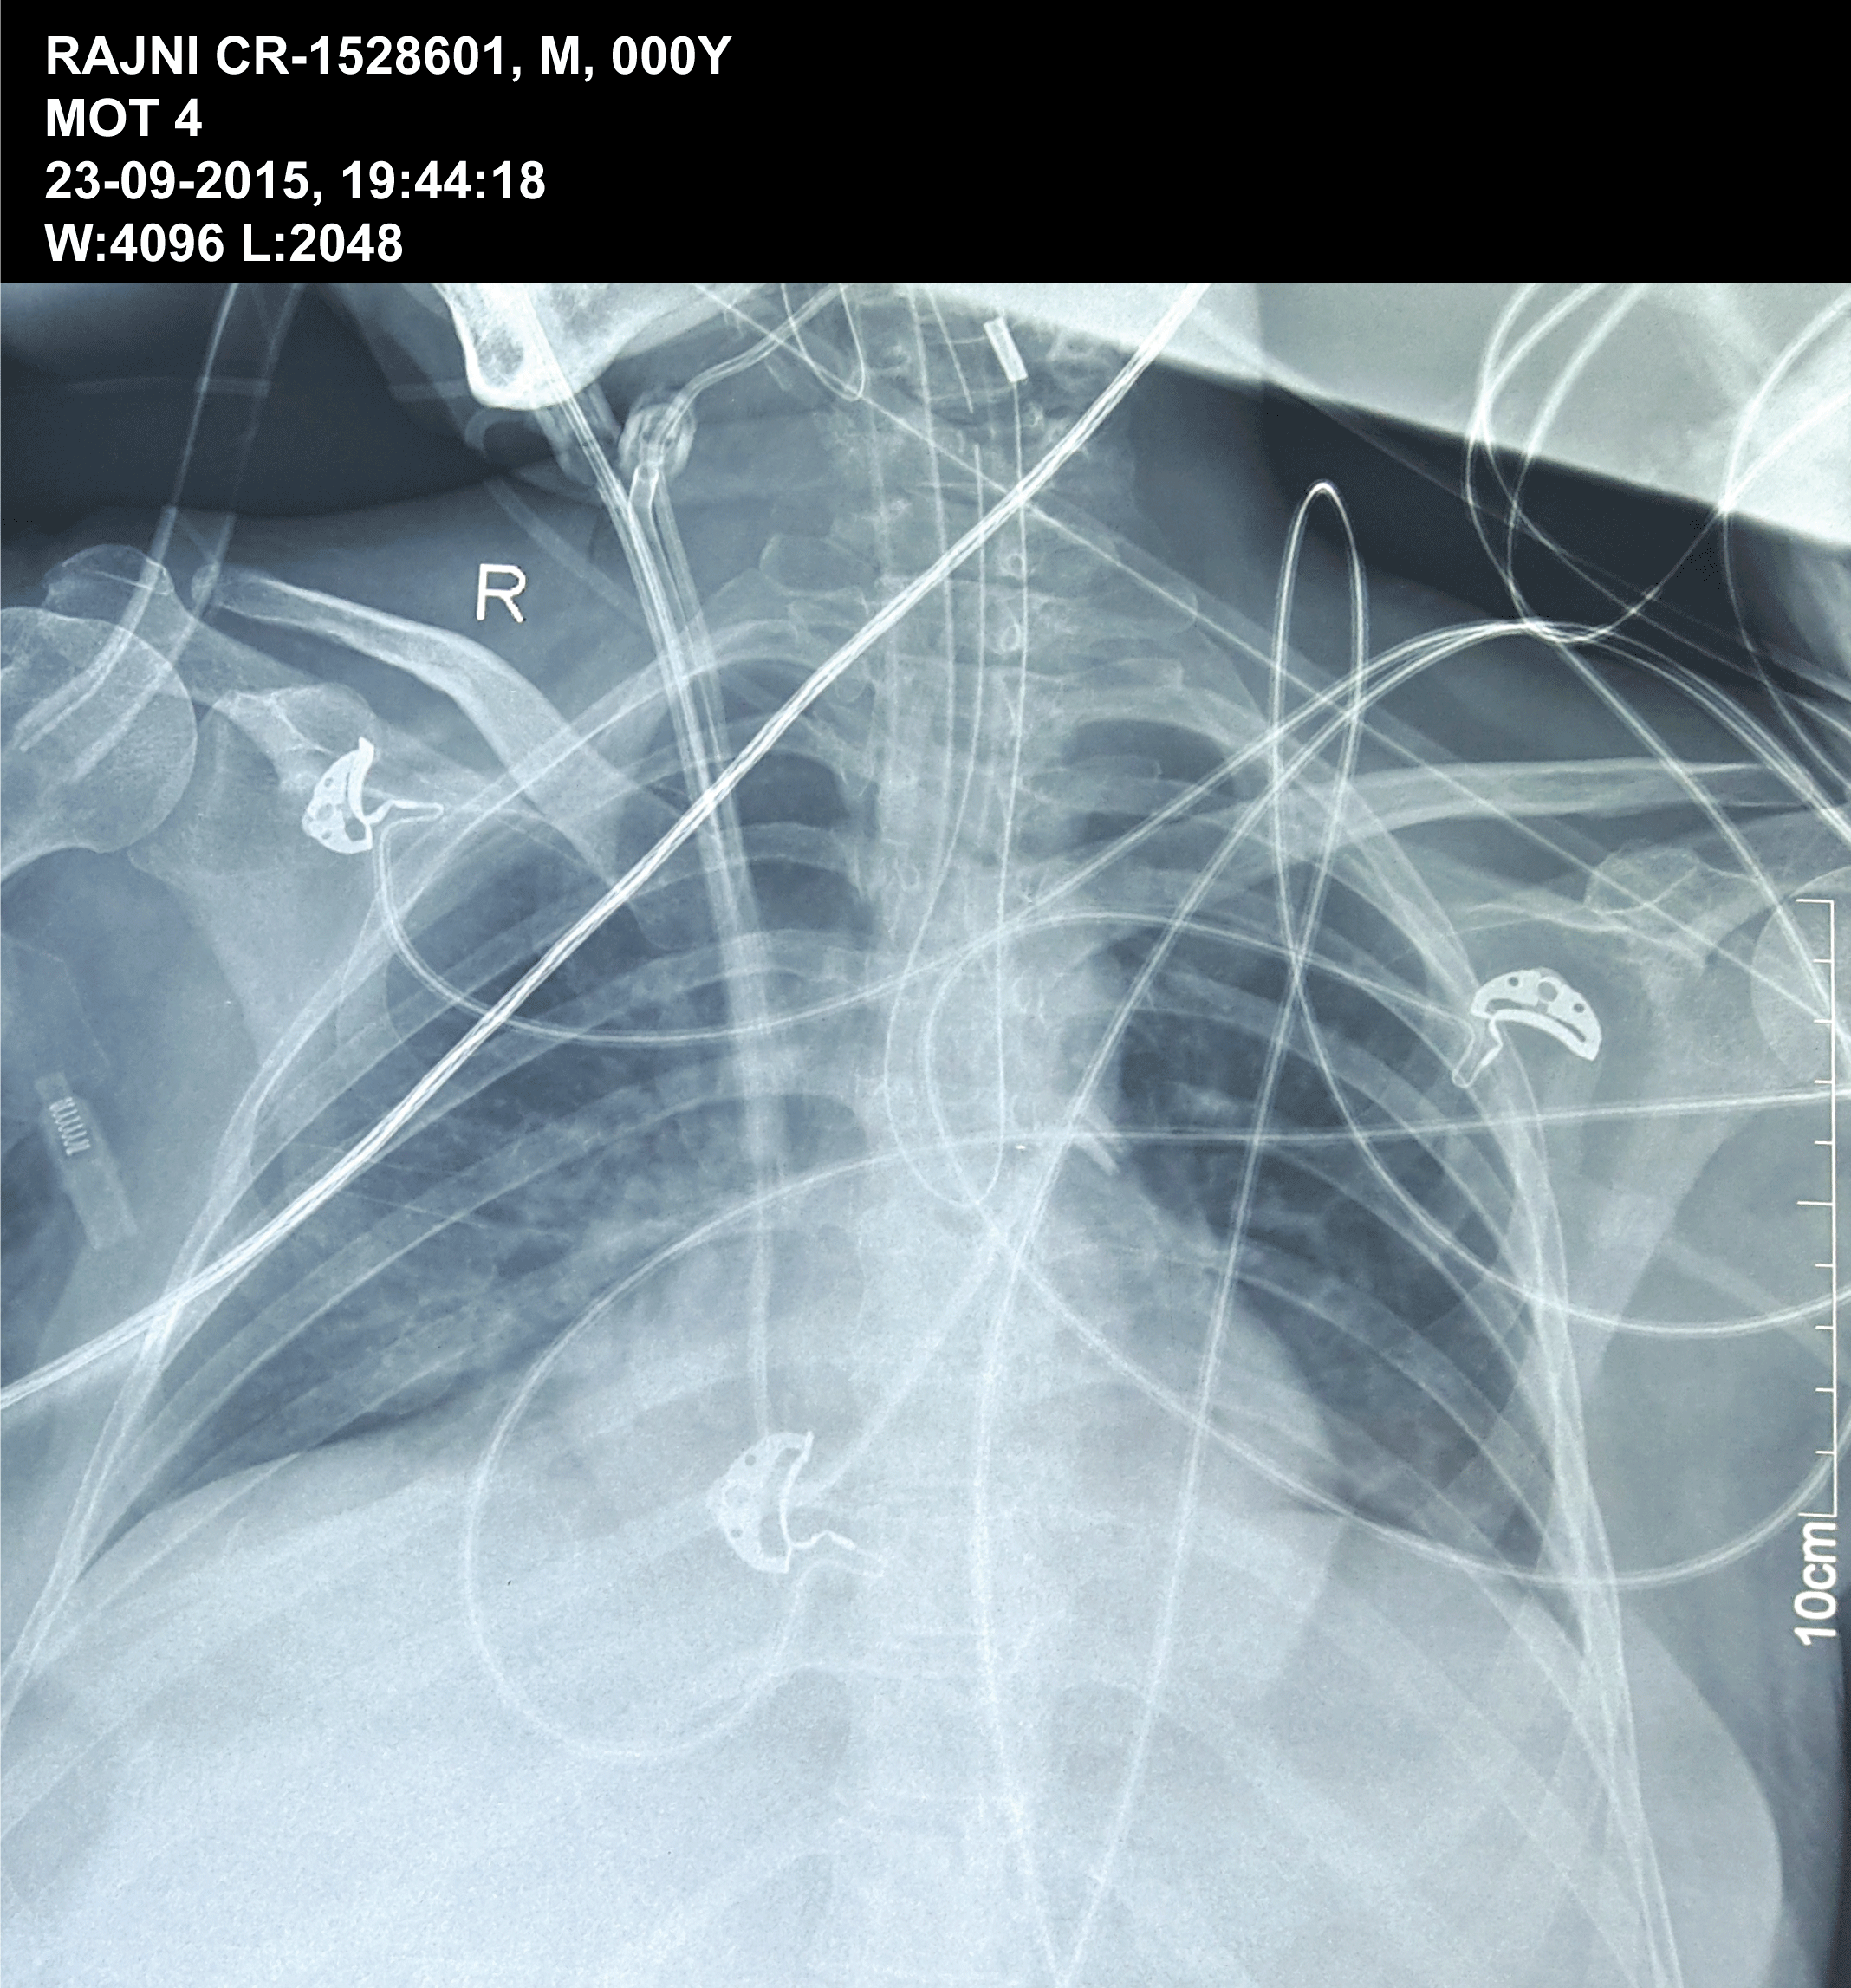

This is a image of an plain X-Ray Chest PA view of a 32 year old female postoperative patient of liver transplant. In this X- ray a nasogastric tube (NG) is seen coiled in the oesophagus which is a rare event. It must be noted that nasogastric tube is coiled as a single U-shaped structure. The tip of NG tube is seen in the upper oesophagus. Normally it gets coiled in the mouth while being inserted through the nose.

Figure 1: This is a image of an plain X-Ray Chest PA view of a 32 year old female postoperative patient of liver transplant. In this X- ray a nasogastric tube (NG) is seen coiled in the oesophagus which is a rare event. It must be noted that nasogastric tube is coiled as a single U-shaped structure. The tip of NG tube is seen in the upper oesophagus. Normally it gets coiled in the mouth while being inserted through the nose.